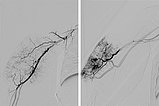

Digitale Subtraktionsangiographie links über die Arteria brachialis und rechts über den Mikrokatheter, welcher in der hypertrophierten Feederarterie am rechten Oberarm platziert wurde.

Digitale Subtraktionsangiographie nach Beginn der Embolisation mit Ethylen-Vinyl-Alkohol-Kopolymer über einen Mikrokatheter mit ablösbarer Spitze. Gleichzeitig Entnahme einer Stanzbiopsie zur histologischen Untersuchung.

Digitale Subtraktionsangiographie nach Embolisation von geschätzt 70 % der arteriellen Tumorversorgung zur Verbesserung des Kasabach-Merritt-Phänomens.